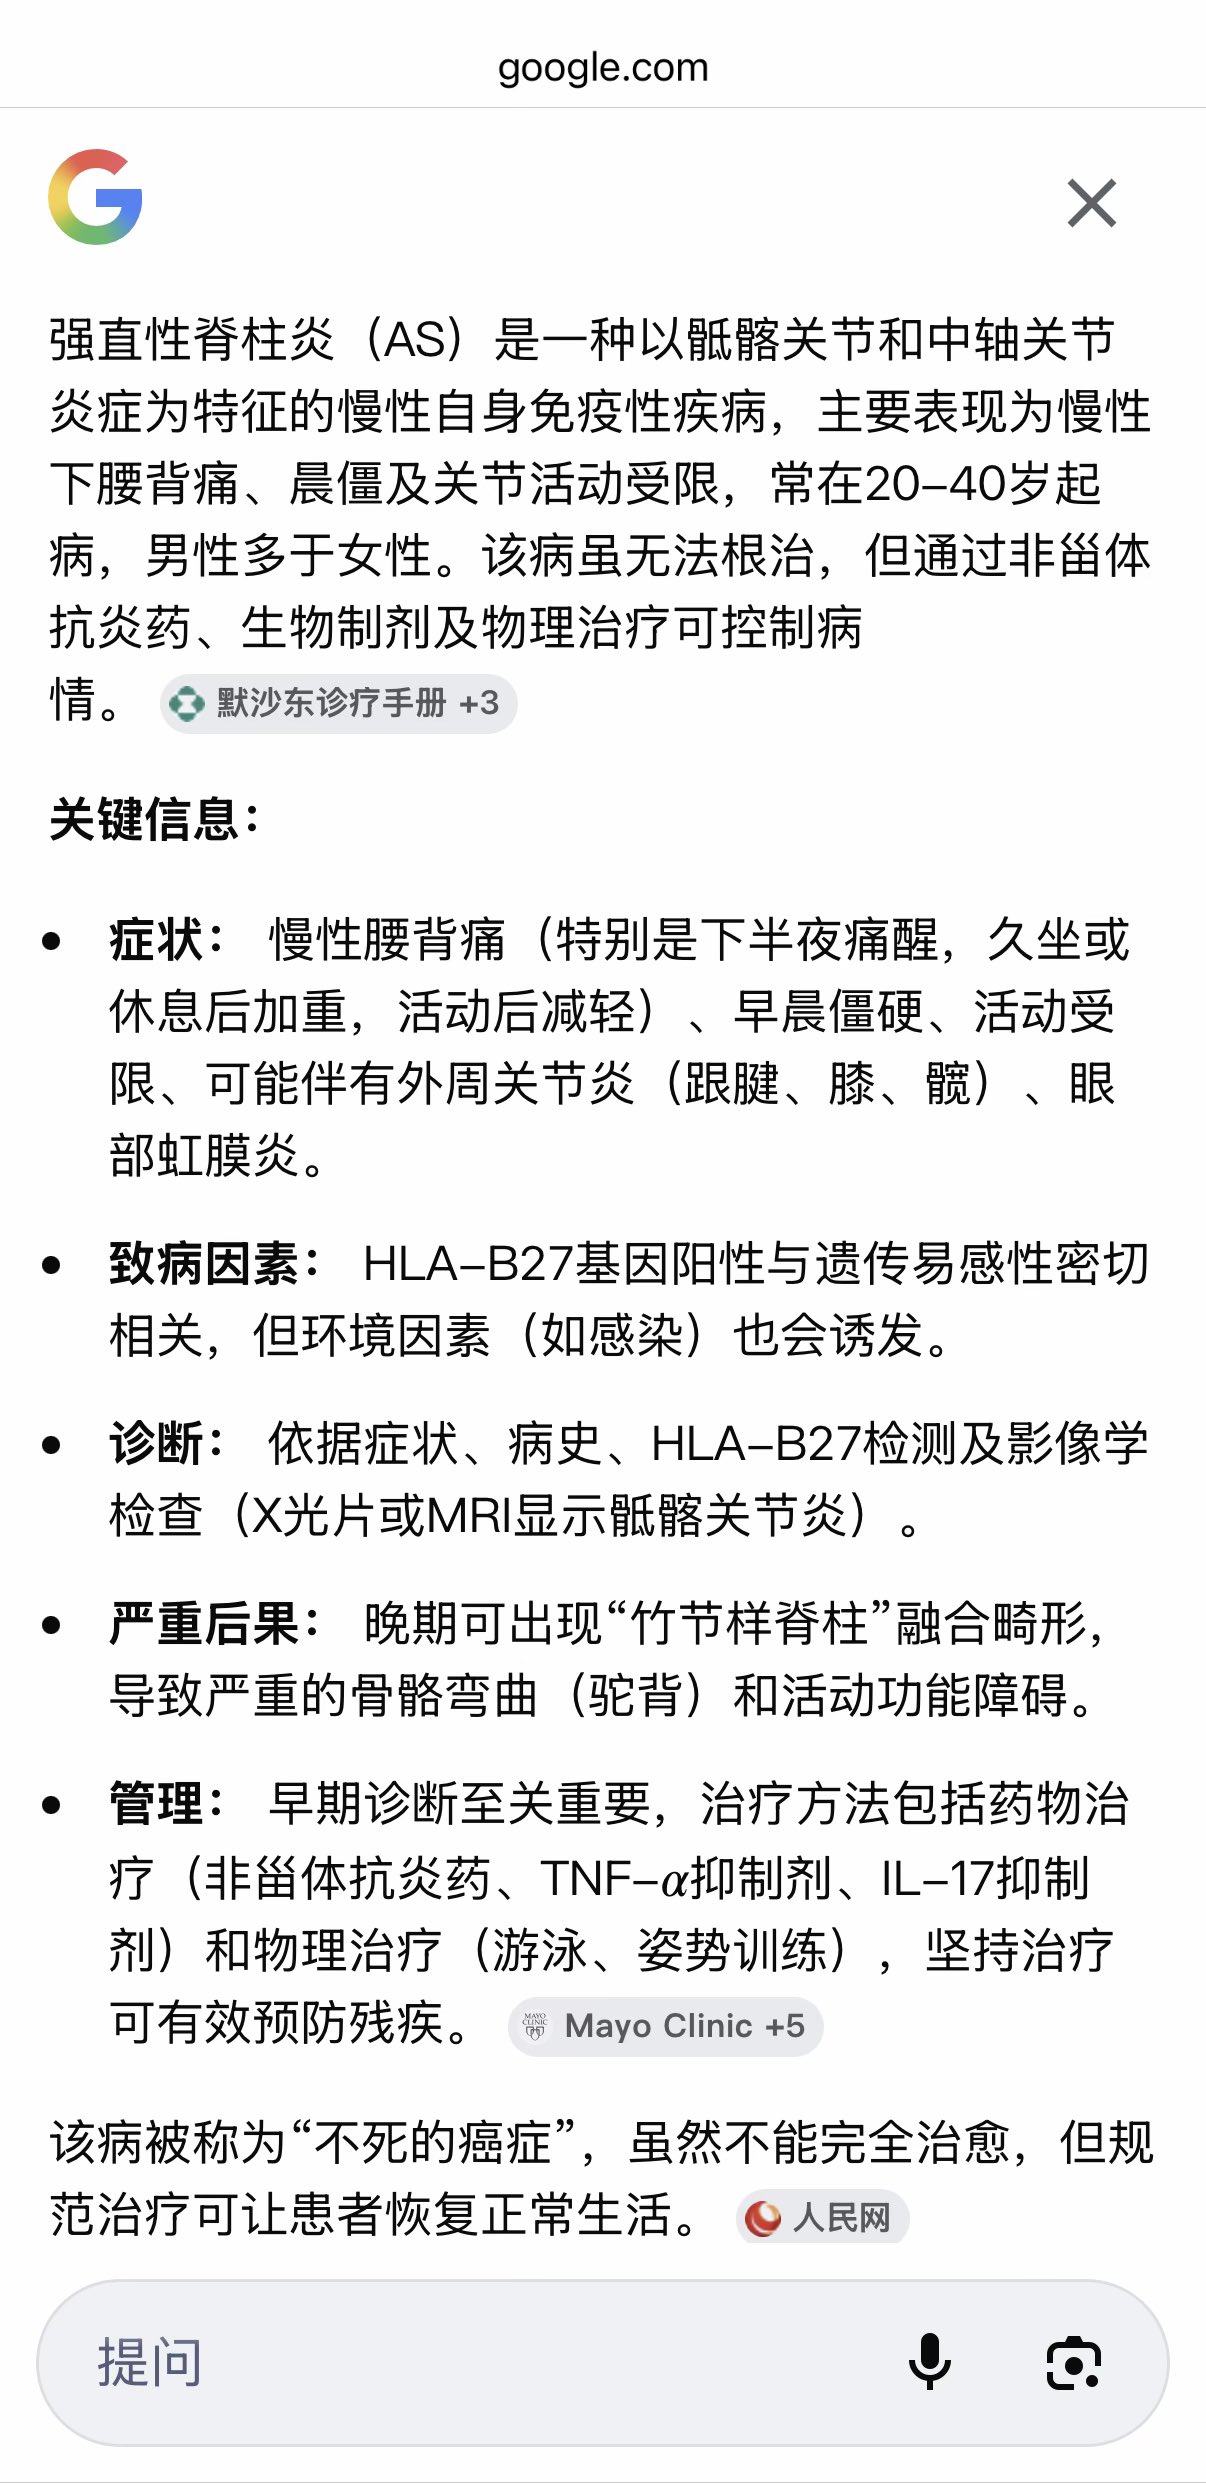

关于后藤提到过的“反解离”

首先,从定义上讲,“反解离(anti-dissociative)”并不是一个标准的医学术语或者广泛认同的药理学分类。在正规资料,比如医学文献、维基百科、精神药理学教科书中,目前并没有“反解离药物”这个正式概念。

看上去像是为了描述某类特定效应而创造的术语(可能是nmda受体活性增强),用来对抗因NMDA受体拮抗剂(比如氯胺酮、DXM、PCP等)引发的解离体验(dissociation)。

那么更常见的是将其归入认知增强剂(cognitive enhancers),特别是改善认知连接性(connectivity)和现实感知(reality testing)的类型。

但其实在药理学上,单纯用“受体激动剂”来逆转“受体拮抗剂”的效应,有时会导致过度激活。

对于NMDA受体而言,过强的NMDA活化本身就与兴奋性毒性(excitotoxicity)和精神病样症状(psychotomimetic effects)有关,比如谷氨酸风暴可以引发严重的焦虑、妄想、乃至癫痫。

也就是说,简单地“激动-解除拮抗”在中枢神经系统是很危险的做法,尤其是对于易感个体(如有精神分裂素质的人)。

科学的处理方式一般是通过更细致的调节,比如微调NMDA/AMPA平衡、调节其他辅助途径(如GABA、5-HT、mGluR受体),而不是简单粗暴地用“NMDA增强剂”去顶回去。

而临床处理药物中毒中,其实医生更常用的做法是保守、支持性的治疗,比如补液,促进代谢,必要时镇静,以及监测生命体征防治并发症。

药物拮抗与受体激动之间,往往牵扯到的是复杂的适应性变化(receptor upregulation/downregulation),

不是简单的“给多一点刺激就能抵消”的关系